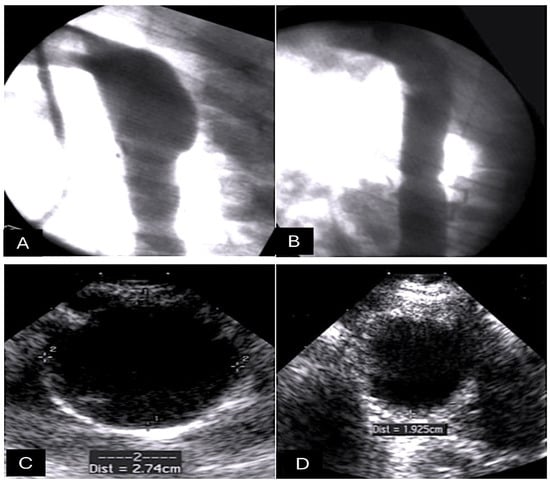

- Nappi, F.; Spadaccio, C.; Fouret, P.; Hammoudi, N.; Chachques, J.C.; Chello, M.; Acar, C. An experimental model of the Ross operation: Development of resorbable reinforcements for pulmonary autografts. J. Thorac. Cardiovasc. Surg. 2015, 149, 1134–1142. [Google Scholar] [CrossRef]

- Nappi, F.; Spadaccio, C.; Fraldi, M.; Montagnani, S.; Fouret, P.; Chachques, J.C.; Acar, C. A composite semiresorbable armoured scaffold stabilizes pulmonary autograft after the Ross operation: Mr Ross’s dream fulfilled. J. Thorac. Cardiovasc. Surg. 2016, 151, 155–164.e1. [Google Scholar] [CrossRef]